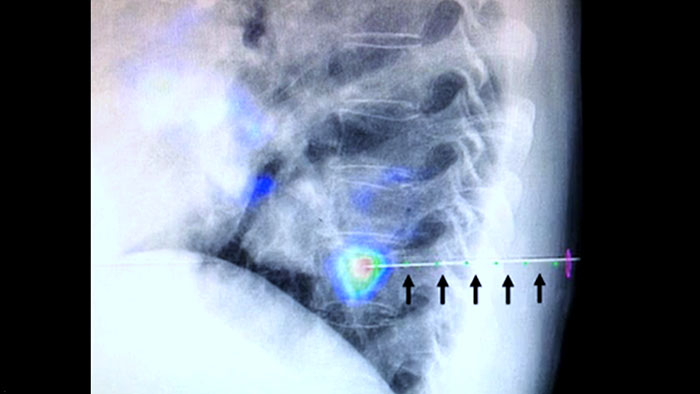

XperGuideでは、事前計画した軌道を透視画像にオーバーレイ表示することで、各ニードルの高精度のライブイメージガイダンスを必要な位置に表示できます³。